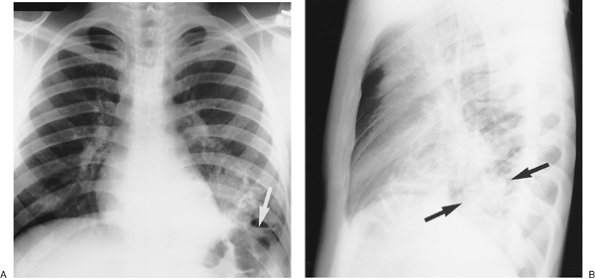

Also referred to as the scimitar syndrome or hypogenetic lung syndrome, pulmonary venolobar syndrome is a form of partial anomalous pulmonary venous return that is accompanied by ipsilateral lung hypoplasia. The anomalous venous return is commonly to the inferior vena cava (Fig. 16-5). The hypoplastic lung (which is almost always right sided) is supplied partly or completely by systemic arteries. The ipsilateral pulmonary artery is diminutive. Associated cardiovascular anomalies are frequent, the most common being atrial septal defect (6). Other associated anomalies include pulmonary sequestration, absence of the inferior vena cava, and accessory diaphragm. Less commonly, the syndrome may involve tracheal trifurcation, eventration and partial absence of the diaphragm, phrenic cyst, horseshoe lung, anomalous superior vena cava, and absence of the left pericardium (7). Bronchial anomalies are common, particularly isomerism (identical right and left branching patterns). The anomalous vein is usually visible on frontal chest radiographs as a broad, gently curved shadow descending to the diaphragm just to the right of the heart (Figs. 16-6 and 16-7). The shadow is shaped like a Turkish sword (a scimitar); thus, the designation scimitar syndrome. Other radiographic findings include a small ipsilateral hemithorax with diminished pulmonary vascularity, shift of the mediastinum toward the involved side, and, often, indistinctness of the cardiomediastinal border on the involved side. The lateral radiograph usually

P.269

shows a retrosternal band of opacification, which is secondary to the shortening of the anteroposterior diameter of the involved lung, and contact of the anterior involved lung with a rotated and shifted mediastinum (8). Anomalous pulmonary venous return can also be an isolated finding, unassociated with other anomalies (Fig. 16-8).

FIGURE 16-6. Pulmonary venolobar syndrome. A: PA chest radiograph of an 11-year-old girl shows a curvilinear band of opacification (arrows) adjacent to the right heart border, representing an anomalous pulmonary vein draining into the inferior vena cava. The vein is shaped like a Turkish sword, giving rise to the name "scimitar syndrome," another term used to describe this entity. Hypoplasia of the right lung is not clearly seen on this view. B: Lateral view shows a retrosternal band of opacification (arrows), created by shortening of the anteroposterior diameter of the right lung, and contact of the anterior right lung with a rotated and shifted mediastinum.